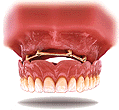

El Implante actúa simulando la función de una raíz, se

oseointegra en su hueso y es un pilar perfecto para muy

distintos tipos de prótesis.

Realizar una prótesis sobre implantes no es tarea fácil, ya que supone un estudio muy profundo y complicado de su estructura óseo-bucal, de su oclusión y de su salud en general entre otros muchos factores. Tan solo su dentista puede determinar la oportunidad de este tipo de tratamientos que, entre otras cosas requieren una alta preparación del Cirujano, Odontoestomatólogo y del Técnico dental.

A continuación podrá ver algún tipo de prótesis sobre

implantes:

Antes y después del

tratamiento.